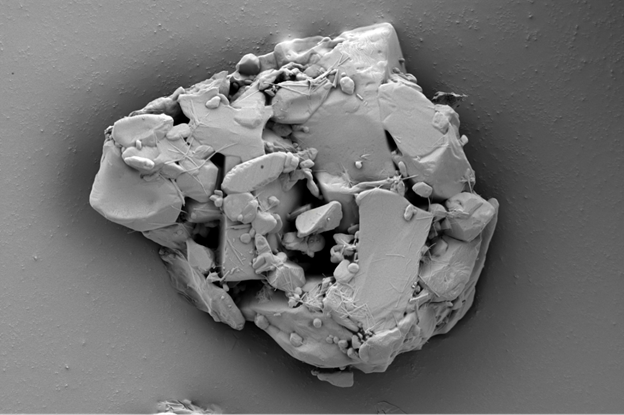

Для систем с модифицированным высвобождением СЭМ раскрывает взаимосвязь между внутренней архитектурой и кинетикой высвобождения. Например, хлорид калия в исходном состоянии характеризуется кубической кристаллической решеткой (рис. 2а).

При разработке таблеток с пролонгированным высвобождением на основе гидроксипропилметилцеллюлозы (ГПМЦ) методом СЭМ было установлено, что измельченные частицы хлорида калия (сохраняющие фрагменты кубической формы) равномерно распределены и прочно связаны непрерывной гелевой матрицей ГПМЦ. Граница раздела фаз характеризуется хорошей адгезией, структура отличается плотностью и низкой пористостью (рис. 2b). Такая плотная упаковка замедляет проникновение жидкости и обеспечивает диффузионно-контролируемое высвобождение, что согласуется с моделью Хигучи – математическим уравнением, описывающим высвобождение лекарственного вещества из твердой матричной системы.

Рис. 2а — Кубические кристаллы хлорида калия.

Рис. 2b — Таблетка хлорида калия с пролонгированным высвобождением: частицы АФИ (сохранившие части кубической огранки) интегрированы в плотную гелевую матрицу ГПМЦ. Изображение получено с помощью СЭМ LANSEM 30.